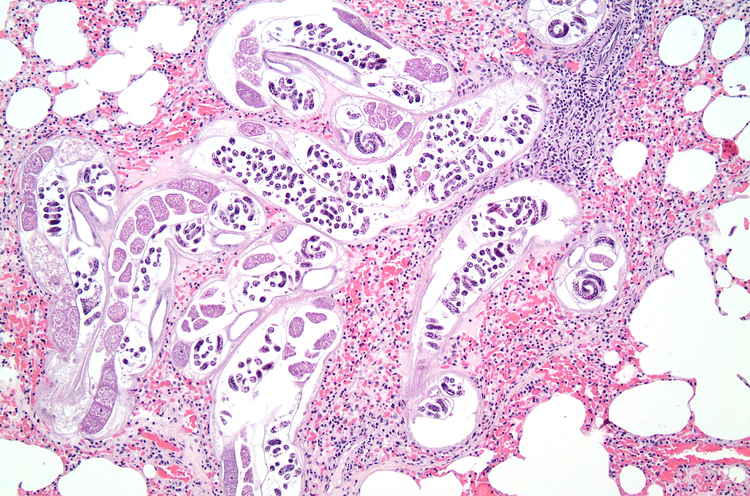

Frisch verendete Tiere werden von den Wattenjagdaufsehenden geborgen. Anschließend werden sie durch das Lebensmittel- und Veterinärinstitut Oldenburg abgeholt und dort untersucht. Äußere oder innere Verletzungen, ein starker Parasitenbefall sowie krankhafte Organveränderungen können durch eine umfassende pathologische Untersuchung festgestellt werden. Darüber hinaus werden die Organe auf Krankheitserreger (Bakterien, Viren, Pilze, Parasiten) und auf Schadstoffe untersucht.

Einige der untersuchten Tiere wiesen Verletzungen auf, deren Ursache jedoch nicht ermittelt werden konnte. Die bisherigen Untersuchungen auf Krankheitserreger (Bakterien, Viren und Parasiten) haben keine Hinweise für das Vorliegen auf Infektionskrankheiten ergeben, die die Bestände der kleinen Meeressäuger gefährden (beispielsweise Staupeviren, Influenza-A-Viren, Erreger des Rotlaufs). Allerdings wurde eine Vielzahl von Bakterien gefunden, die zu Erkrankungen bei Einzeltieren führen können. Hier sind beispielhaft die Nachweise von Brucellen (Brucella pinnipedialis) und Streptokokken (Streptococcus phocae) zu nennen. Darüber hinaus waren viele Tiere mit Parasiten infiziert. Ob es sich bei dem Befall des Bestands noch um ein normales Phänomen handelt (In Wildtiere sind sehr häufig Parasiten zu finden) oder ob der starke Befall auf eine Störung der Gesundheit der Population hinweist, soll in weiterführenden Untersuchungen geklärt werden.